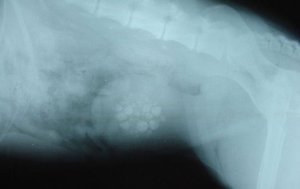

Ультразвуковое исследование мочевого пузыря и почек позволит оценить размеры камней и выявить песок в этих органах.

При необходимости могут быть назначены рентгенография и компьютерная томография для подтверждения заболевания.